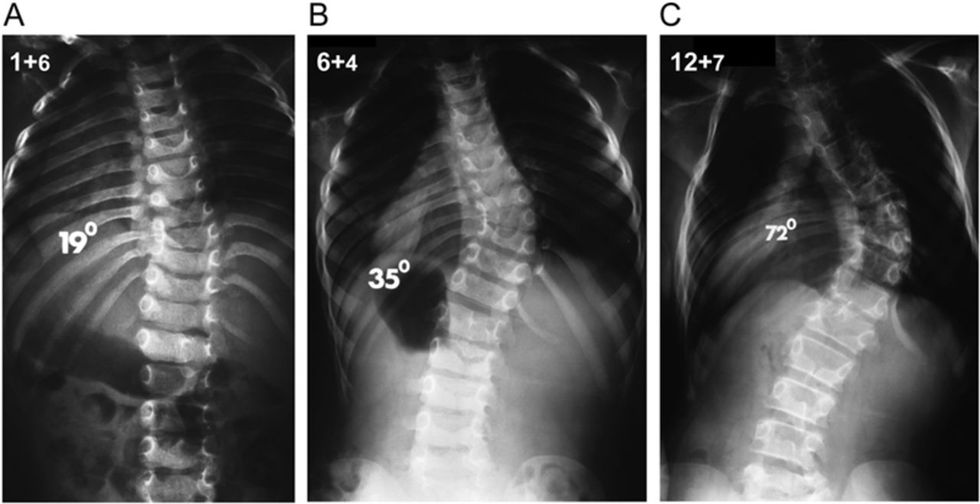

The x-rays revealed that my right side was not bigger because I was athletic, but instead a case of Idiopathic Scoliosis with a 38-degree curvature of the spine.

Surgery is only an option for individuals with curves of 50 degrees or higher. By the time I was diagnosed, I had pretty much stopped growing. This meant that my bones and muscles were basically what they were going to be.

At its highest, my curve was 38 degrees. It is currently at 34 degrees following a few rounds of physical therapy.

Notice that my back is generally (34 degrees!) slanted to the right. My x-rays resemble a question mark.